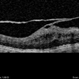

- vitreoschitic membrane

- vitreoschisis, myopic traction maculopathy

- Triamcinolone enhanced visualization of vitreoschisis membrane and removal in a case of myopic traction maculopathy.